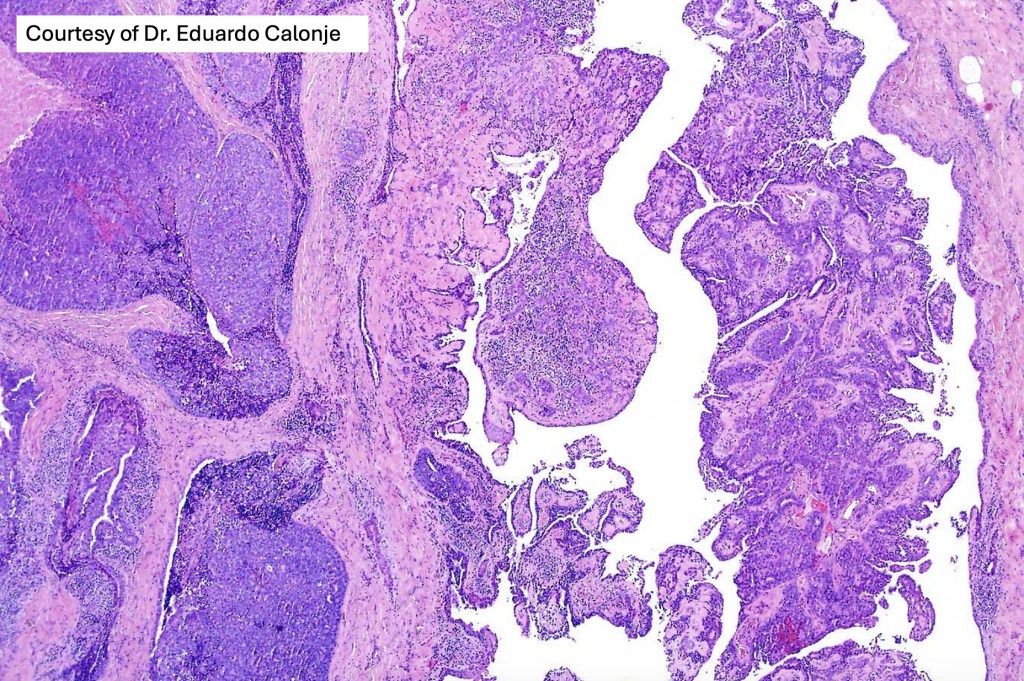

Histological features

•Frequently circumscribed solid/cystic dermal nodule, infiltrative margin rare

•Papillary component (may include pseuopapillae & true papillae with a fibrovascular core)

•Back-to-back glands with double-layered epithelium

•Variable necrosis & lymphovascular invasion

In the majority of cases, digital papillary adenocarcinoma is easily recognised even at scanning magnification. Very exceptionally, a metastasis from a visceral papillary carcinoma must be excluded. Clinicopathological correlation should resolve the matter. Where doubt remains, identification of a myoepithelial layer and CK7 expression will confirm the diagnosis. Some cases can appear deceptively bland and papillary eccrine adenoma may have to be excluded. Again clinicopathological correlation is valuable as is the identification of true papillae, nuclear pleommorpism and excessive mitotic activity.